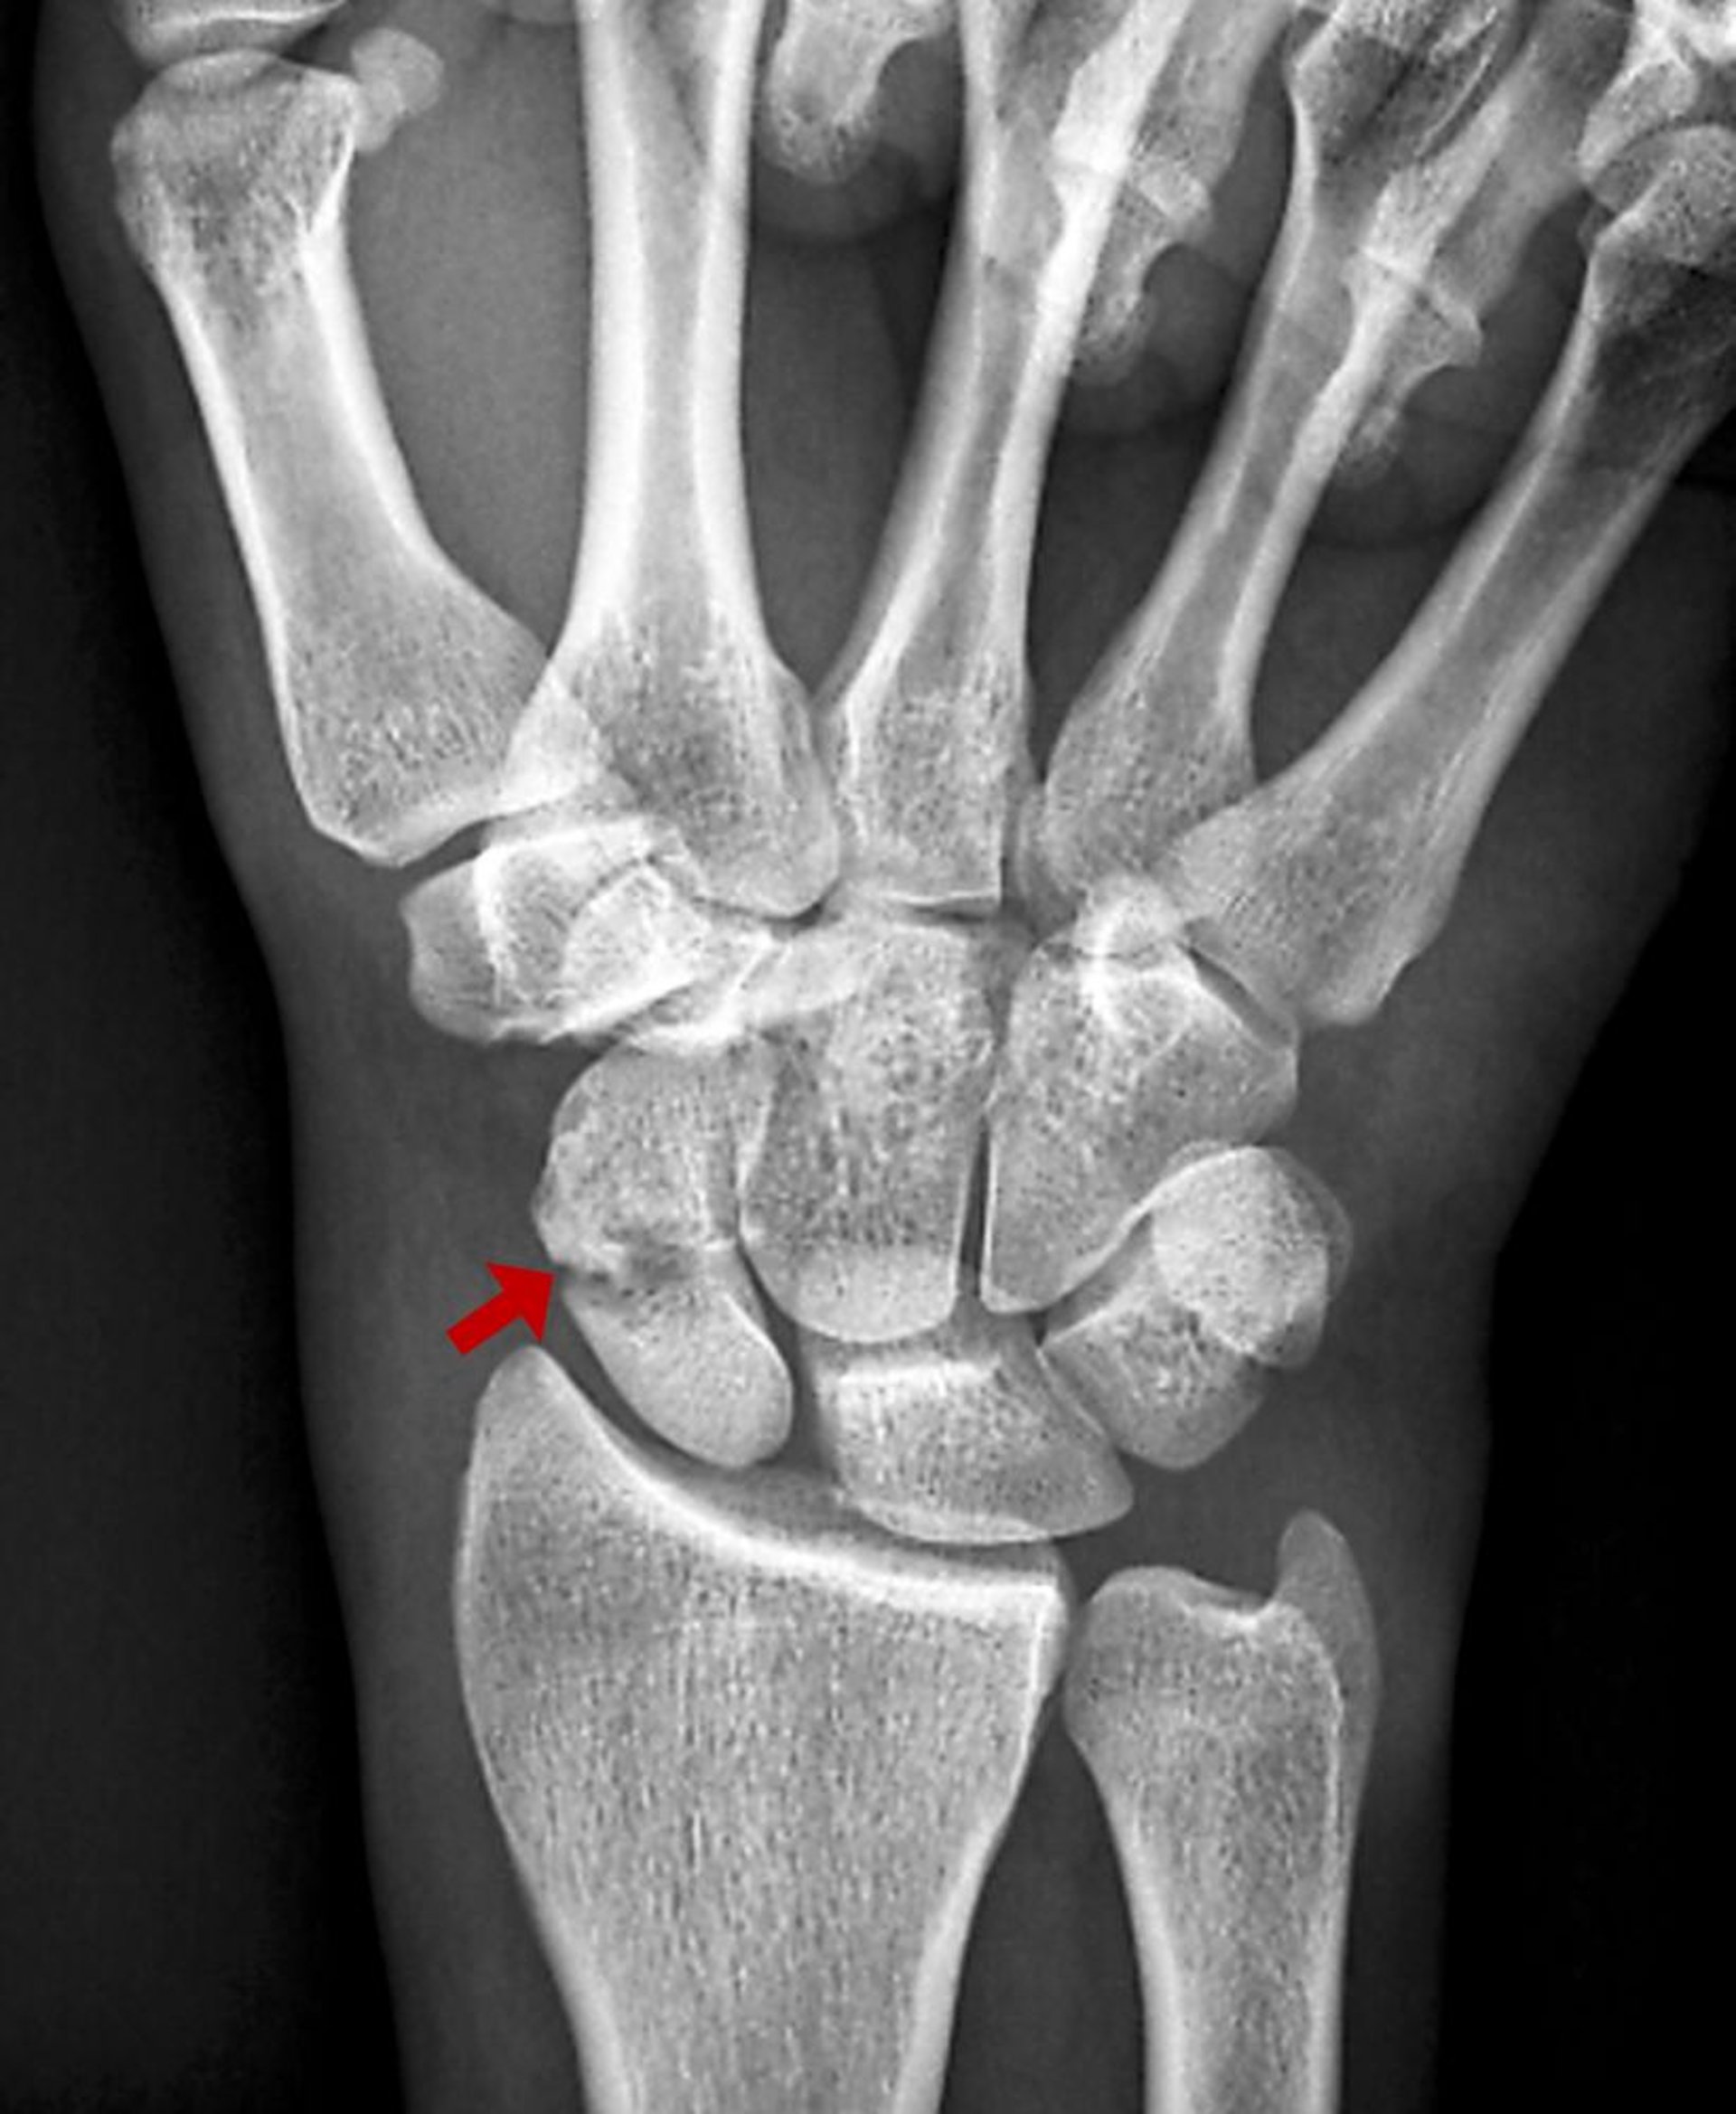

Kahnbeinfrakturen sind üblicherweise Ergebnis von Überstreckung des Handgelenks. Es kann sein, dass sie nicht bei den ersten Röntgenaufnahmen sichtbar sind. Komplikationen können schwerwiegend sein.

Das Kahnbein ist der am häufigsten verletzte Handwurzelknochen. Kahnbeinfrakturen werden in der Regel durch eine Überstreckung des Handgelenks verursacht, typischerweise während eines Sturzes auf die ausgestreckte Hand. Sie können die Blutversorgung zu dem proximalen scaphoideum stören. Die Osteonekrose gehört zu den häufigen Komplikationen, selbst wenn die Erstbehandlung optimal war, und kann eine die Funktion mindernde degenerative Arthritis des Handgelenks nach sich ziehen.

Zunächst werden Röntgenaufnahmen (anteroposteriore, laterale und schräge Ansichten) angefertigt, die jedoch häufig normal sind. Nur etwa 70% der Kahnbeinfrakturen sind auf ersten Röntgenaufnahmen zu sehen (1).